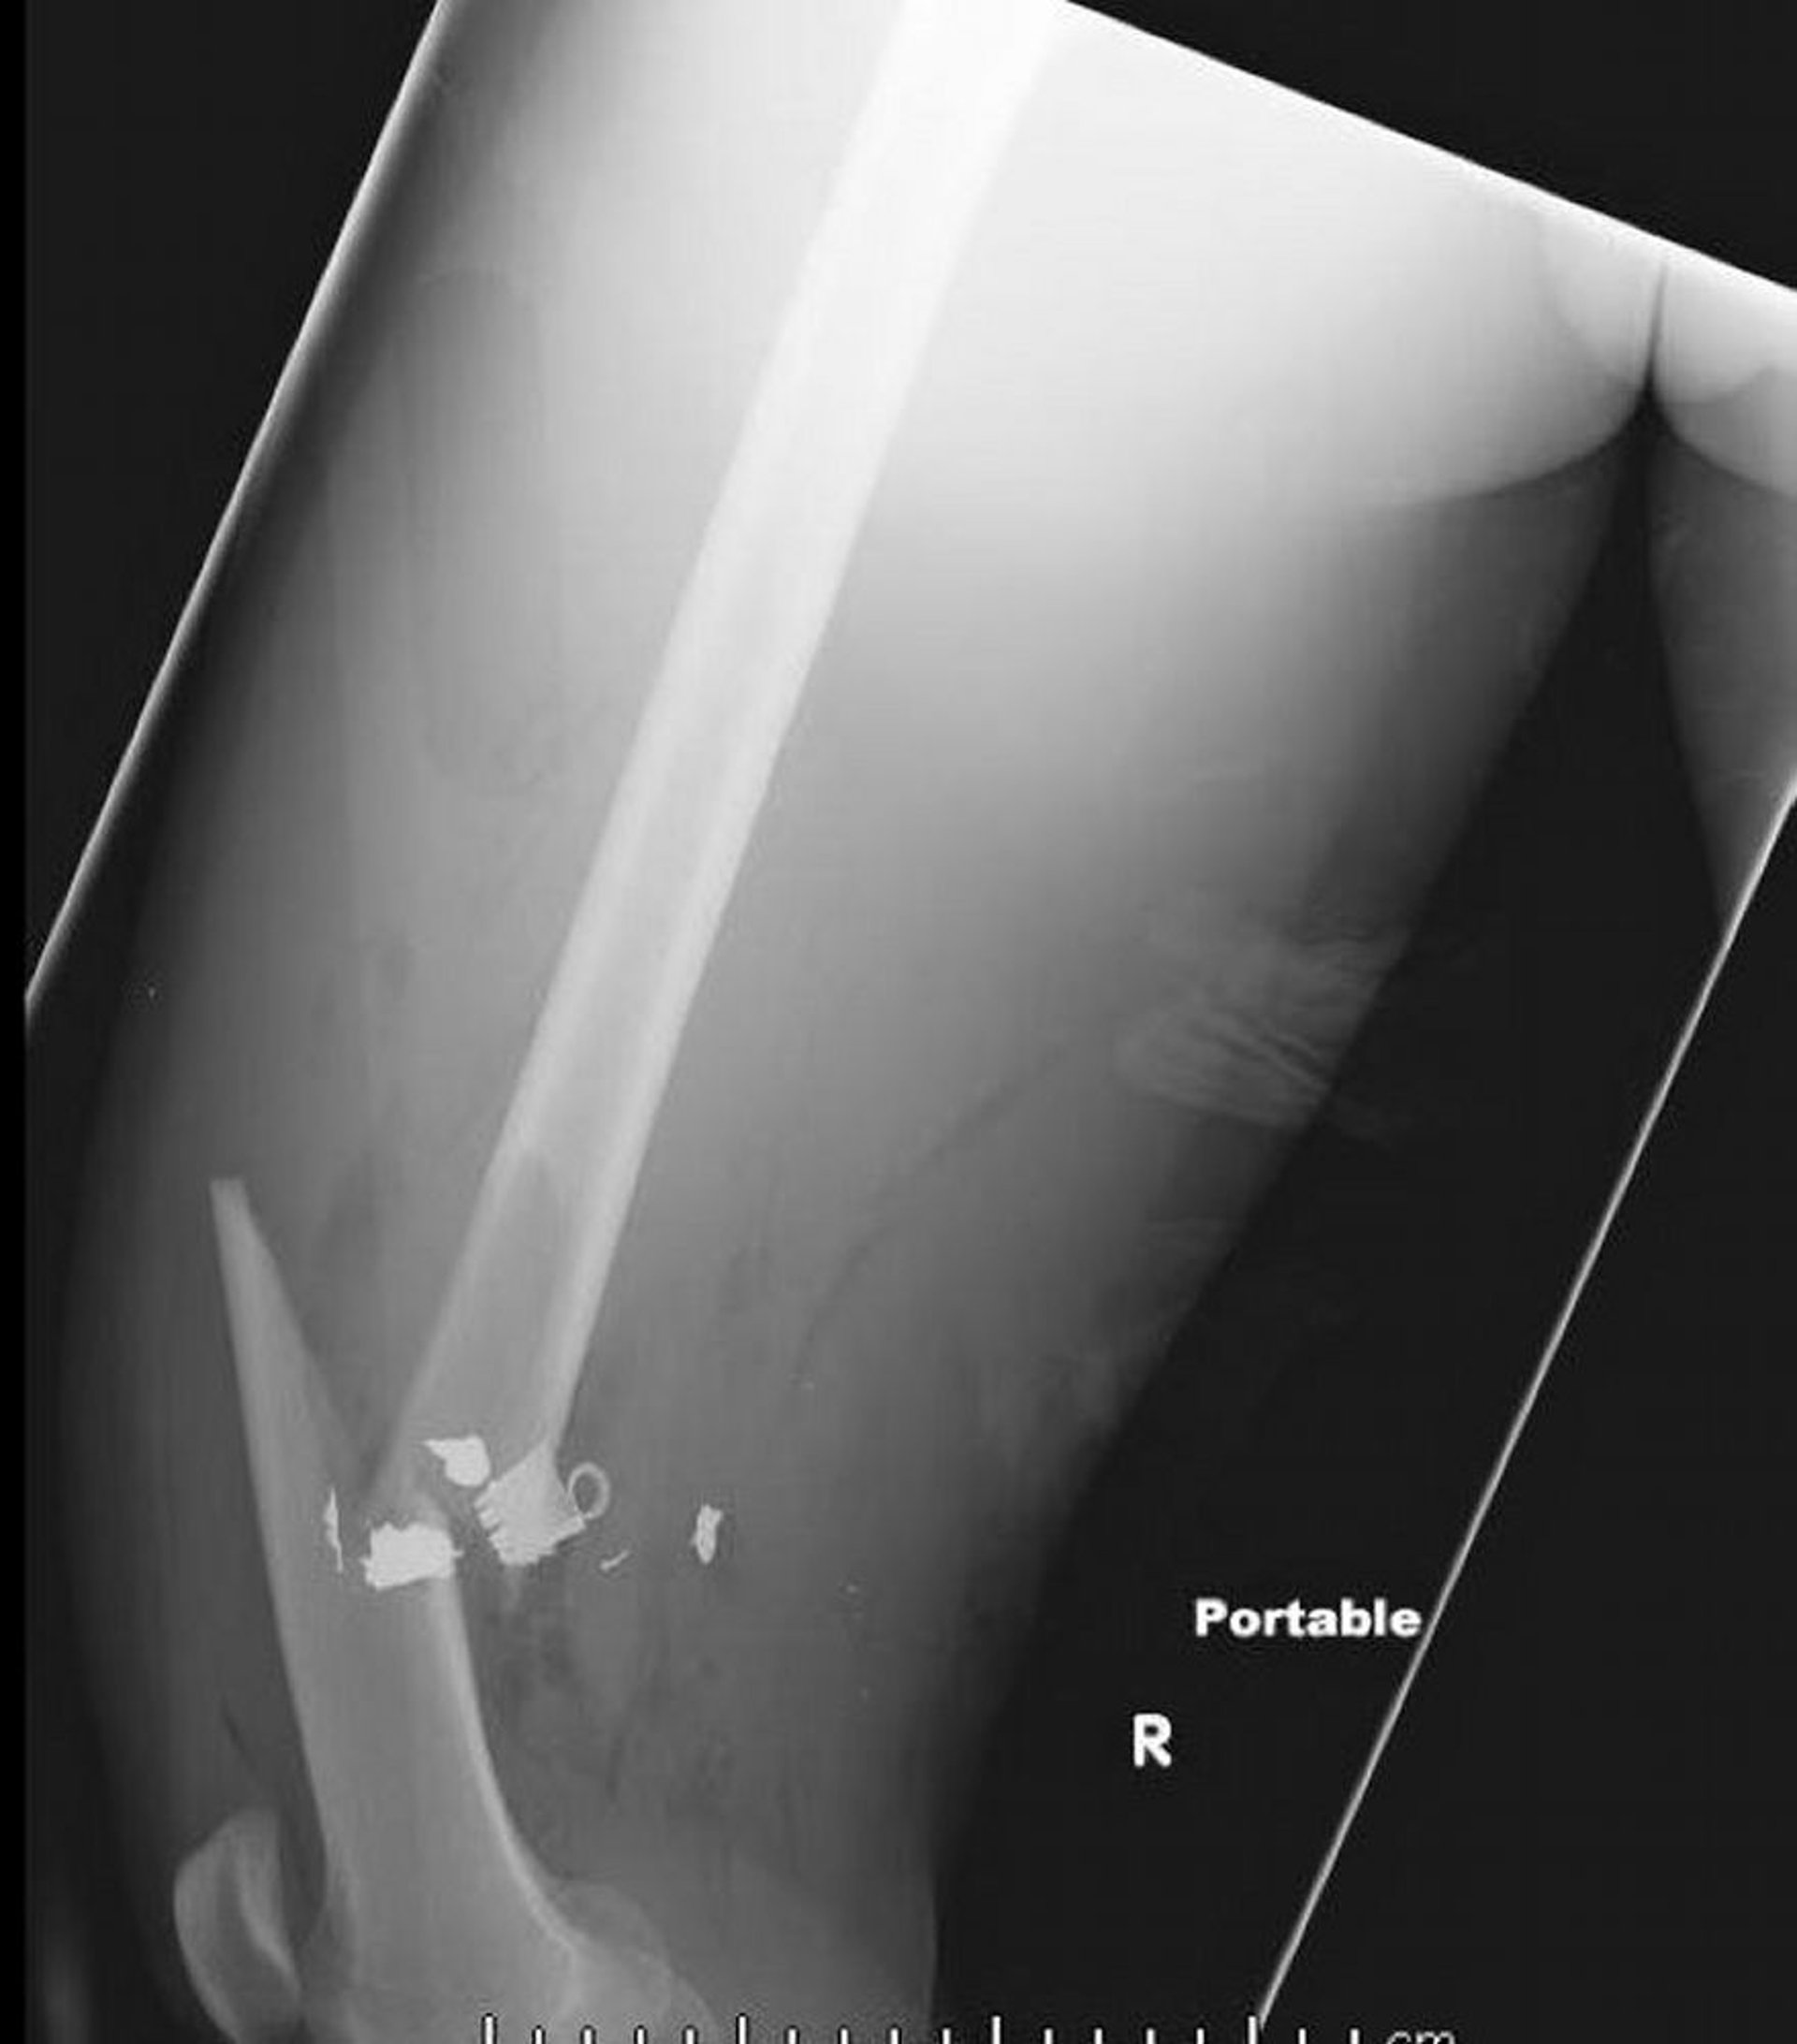

Esta radiografía lateral del fémur muestra una fractura diafisaria del fémur con aire en los tejidos blandos y cuerpos extraños metálicos retenidos.

Image courtesy of Danielle Campagne, MD.